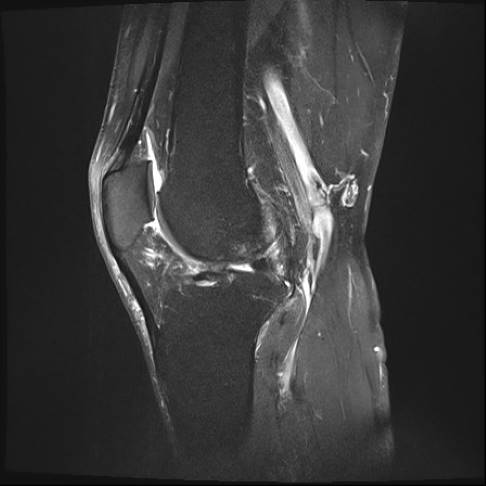

Die Bakerzyste bildet sich zwischen dem inneren Kopf des Zwillingswadenmuskels (M. gastrocnemius) und dem Ansatz des halbmembranösen Muskels (M. semimembranosus). An dieser Stelle weist die Gelenkkapsel eine Schwachstelle auf, durch die die Gelenkflüssigkeit bei erhöhtem Druck entweichen kann. Dies kann der Arzt im Rahmen der Diagnose mittels Ultraschall oder MRT sichtbar machen.